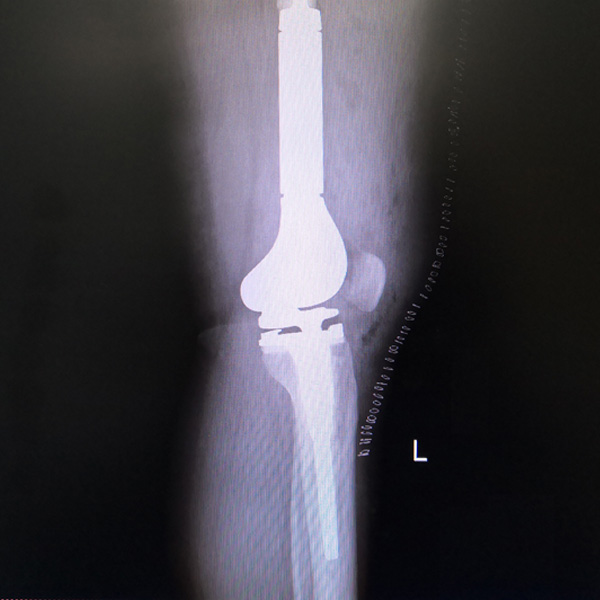

骨肉瘤手術

患者張某,女,14歲,診斷為“左股骨遠端骨肉瘤”,當地醫院因為醫療技術和能力的限制,只能考慮截肢手術。患者家屬通過平臺推薦,指定到哈......